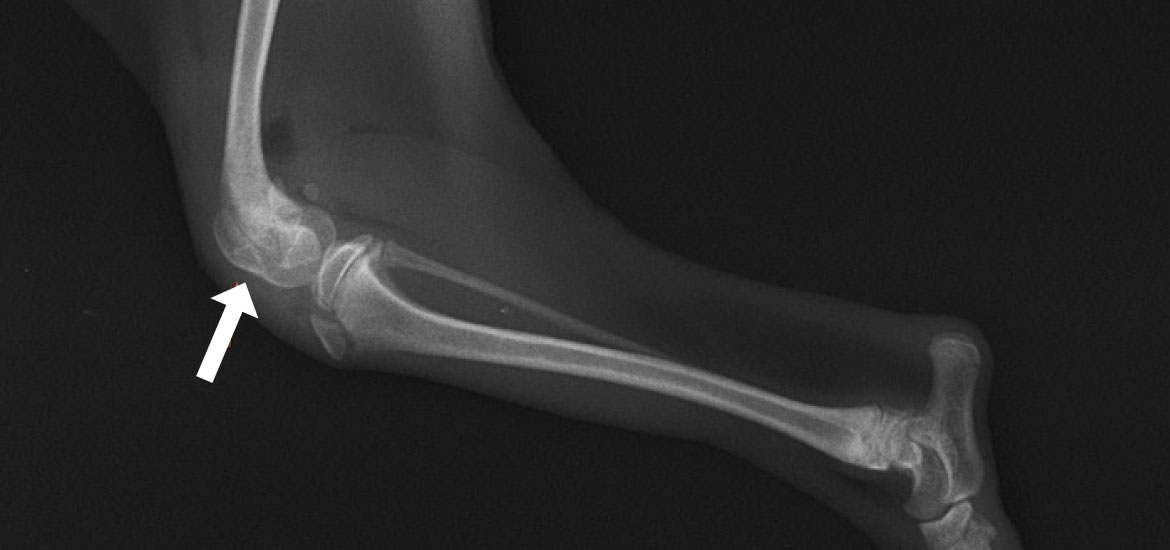

内方脱臼(右後肢)

膝蓋骨が内側(内方)に変位しています -

膝蓋骨が正常な位置(正中)に整復されています